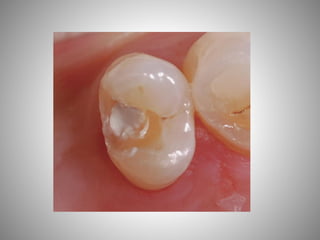

• SIZE OF THE EXPOSURE AND PULPAL HEMORRHAGE:

• The size of the exposure, the appearance of the pulp, and the

amount of bleeding are valuable observations in diagnosing the

condition of the primary pulp

• The most favorable condition for vital pulp therapy is the small

pinpoint exposure surrounded by sound dentin. However, a true

carious exposure, even of pinpoint size, will be accompanied by

inflammation of the pulp, the degree of which is usually directly

related to the size of the exposure